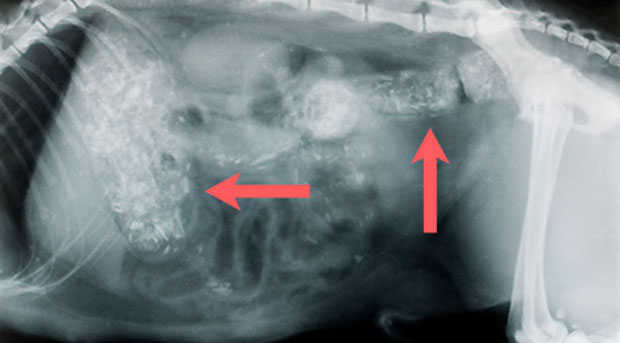

Tumoren in Brust-und Bauchraum (Metastasierung weit fortgeschritten)